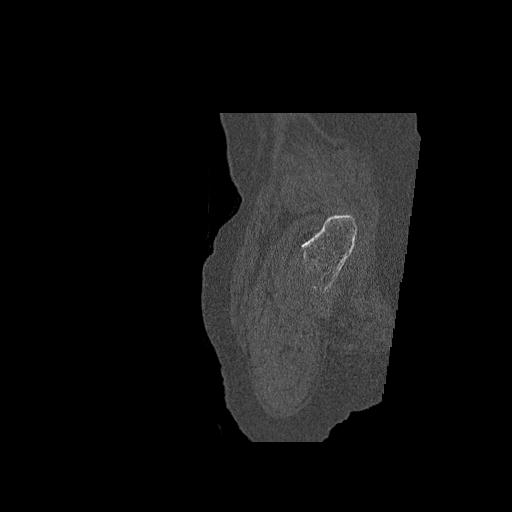

49554 3/13 膝 4R 3/16 4R 1/18 2R 78歳男性 膝蓋骨骨折